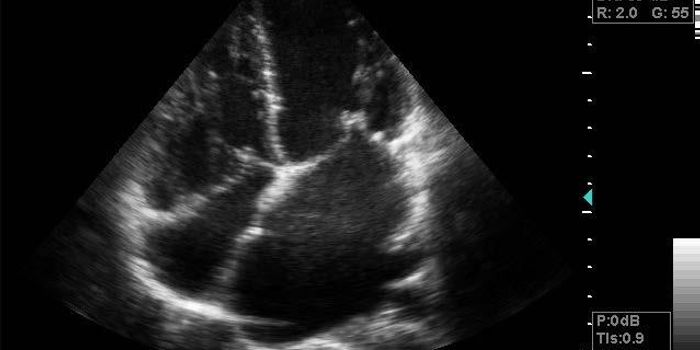

JUN 23, 2017Health & MedicineDo breast implants skew the results from an electrocardiogram (ECG) reading leading to a false diagnosis of a heart atta ...

DEC 10, 2018Health & MedicineIf you or a loved one has been scheduled for a treadmill stress test, you may be wondering what you can expect. The proc ...

DEC 12, 2018CardiologyMany people who experience symptoms like difficulty breathing, fatigue and tightness in the chest during physical activi ...